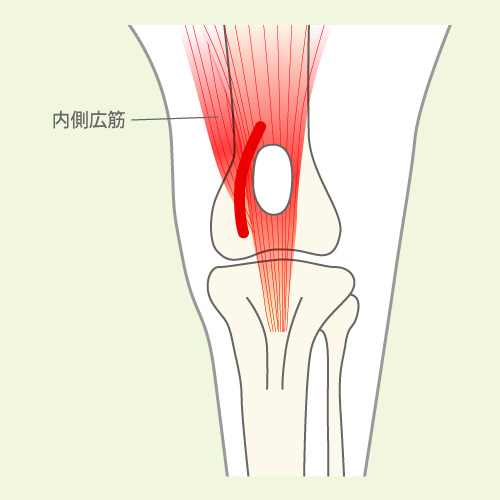

膝関節伸展機構単位で治療内容を検討します。膝関節伸展機構単位とは、膝の曲げ伸ばしに直接関わる解剖学的構造をまとめたもので、下の図のような筋、骨格で構成されています。膝関節伸展機構単位が、大腿骨に対して真正面に位置することが重要で、それによって大腿四頭筋の収縮が正しく伝わり、正常な膝関節の伸展を可能としています。手術では、膝関節伸展機能単位をいかに大腿骨の正面に持っていくかがカギとなります。

膝蓋骨脱臼症例では、膝関節伸展機構単位のどこかの異常によって膝のお皿が脱臼しています。異常の場所や程度は個々の症例によって様々で対応も異なります。

膝蓋骨を脱臼させる方向に牽引する筋肉を切断し他の部位に移動します。大腿四頭筋の作用軸を矯正することで、膝蓋骨を内/外側方向へ過剰に牽引する力を中和する術式です。